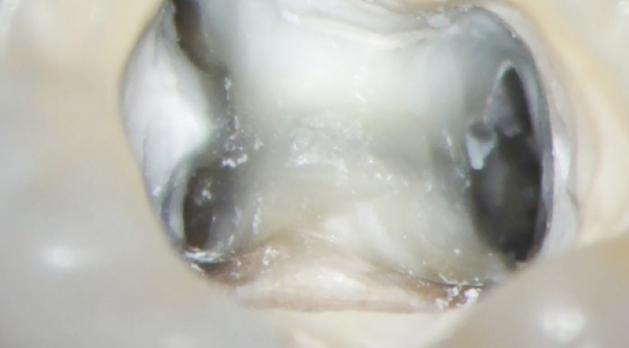

Het succesvol vinden van alle wortelkanalen is cruciaal voor een goede endodontische behandeling. Wanneer delen van het wortelkanaalstelsel onbehandeld blijven, kunnen periapicale laesies blijven bestaan. Deze nascholing bespreekt uitgebreid de hulpmiddelen en technieken die tandartsen kunnen inzetten voor een effectieve kanaallokalisatie.

In blok A wordt ingegaan op het belang van goed zicht en vergroting tijdens de behandeling. Hierbij staat het gebruik van de operatiemicroscoop centraal, vanwege de parallelle lichtbundel en variabele vergroting. Verder worden aanvullende technieken en hulpmiddelen besproken die samen bijdragen aan een optimale visualisatie van het werkgebied.

Blok B richt zich op de praktische toepassing: hoe kennis, ervaring en techniek samenkomen om de eerste stappen van een wortelkanaalbehandeling voorspelbaar en effectief uit te voeren.